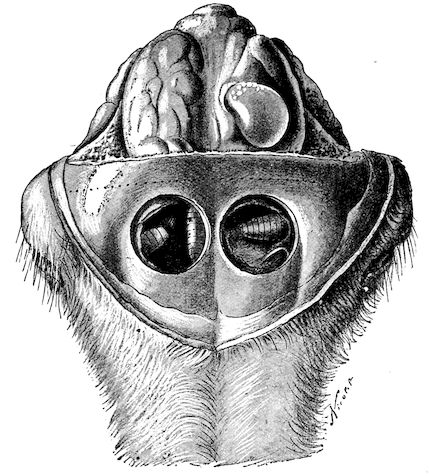

Fig. 8.—Transverse section through the middle region of the face in a pig suffering from osseous cachexia.

18In the final stages, the bones may be cut with a knife, and a time arrives when bony tissue seems completely to have disappeared; thus, as shown in Fig. 8 herewith, it was possible to cut the entire head of a pig into thin slices without the slightest difficulty. All parts of the head had been affected by the softening change.